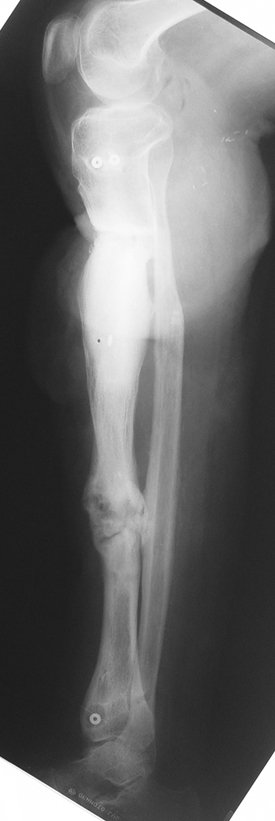

Vaka 2